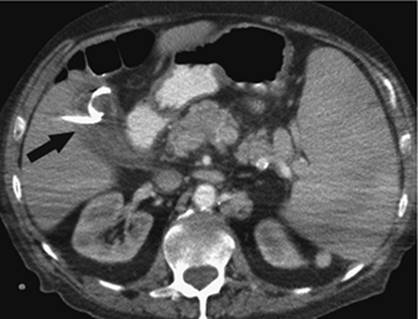

000452

Figure 35.22. Attempted canalization of the portal vein during a transjugular intrahepatic, portacaval shunting (TIPS) procedure. This CO2 injection identifies canalization of the hepatic artery (black arrow).

Puncturing the portal vein has proved to be difficult in some cases. Thrusting a large needle blindly through the liver parenchyma can cause a host of complications including bleeding from the liver capsule if the needle perforates the capsule of the liver. Hemobilia can be seen if the needle perforates a bile duct in close proximity to a vascular structure. The needle may leave the capsule of the liver and puncture adjacent organs including the intestine, gallbladder, kidney, and aorta, among others (Figs. 35.22–35.24).

000454

Figure 35.23. Attempted canalization of the portal vein during a transjugular intrahepatic, portacaval shunting (TIPS) procedure. The tip of the cannula is in the renal pelvis (black arrow).

000459

Figure 35.24. Attempted canalization of the portal vein during a transjugular intrahepatic, portacaval shunting (TIPS) procedure. The tip of the cannula is in the left hepatic duct (black arrow). Contrast is noted throughout the biliary system and into the common bile duct (white arrow).